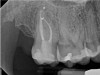

As indicated in Figure 11, the mesial aspect of the distal canal was never touched by instruments, yet he was able to clean, evidenced by the postoperative image. In the past, a case with this level of difficulty would have required at least two appointments, with an interim medication of calcium hydroxide, but the case was treated in a single-visit appointment.  As observed 7 months later (Figure 12), the patient returned completely asymptomatic, and complete bone healing had occurred that exceeded initial expectations.

Fig 12. Case 2: Significant bone loss on the mesial and apical aspect suggested a potential vertical fracture (Fig 9 and Fig 10). Radiographic images were taken immediately postoperatively (Fig 11) and 7 months postoperatively (Fig 12).